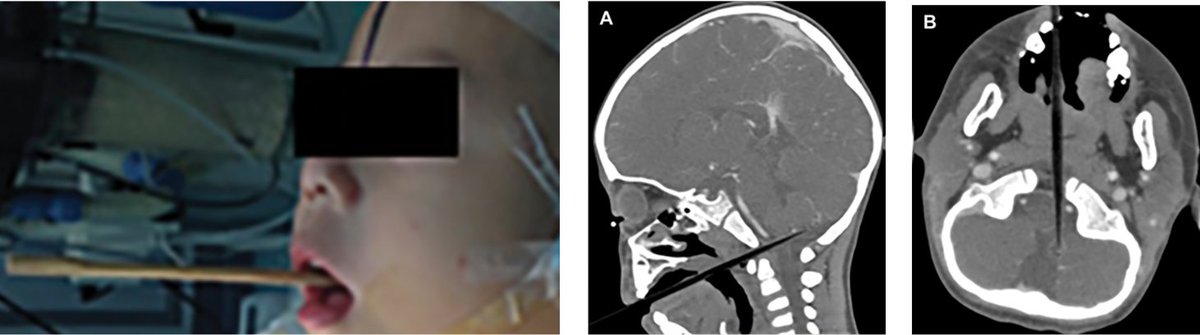

Miracle Outcome: Two-year-old boy was enjoying his meal, fell down, and a single chopstick penetrated though his mouth and went intracranially passing right by his brainstem. 🧵

On admit, his vital signs were stable and he was breathing well. Neurologically, eyes opened to pain, he was confused, and he did localize symmetrically. Thoughts on management? (not my case, reference to follow).

Read 4 tweets